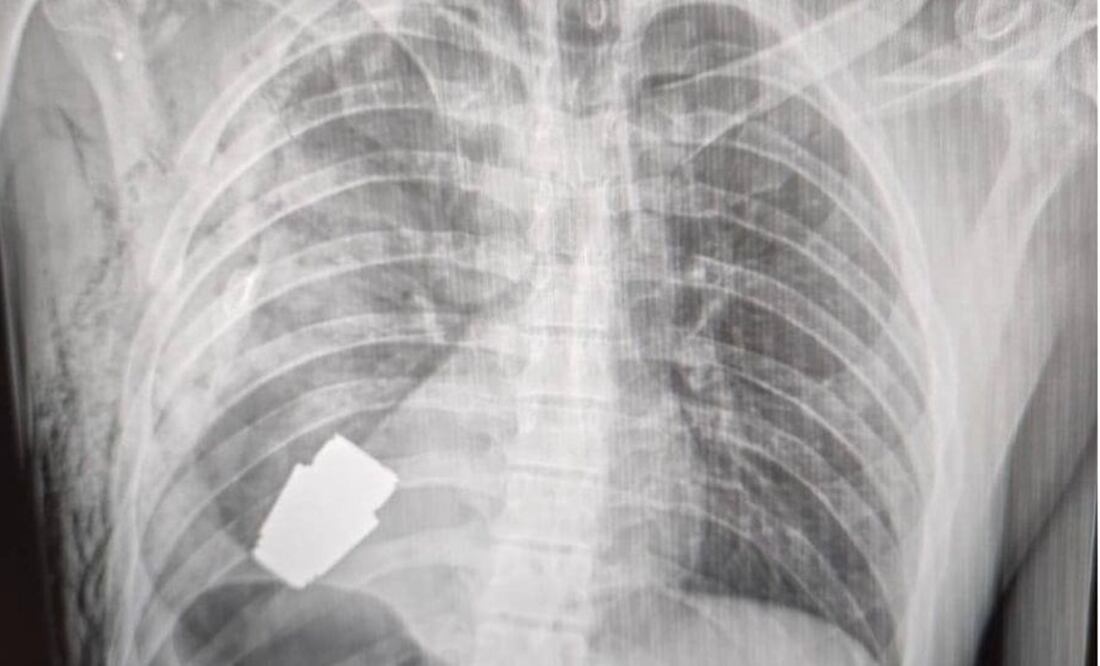

El gobierno ucraniano describió como un "susto afortunado" la terrible experiencia por la que tuvo que pasar un soldado herido, a quien le extrajeron con éxito una granada que se encontraba en su pecho.

El resultado de la delicada operación fue dado a conocer por la viceministra de Defensa, Hanna Maliar, quien publicó en redes sociales que "no todas las heridas en la zona del corazón son letales".

Agregó que la granada fue extraída bajo la supervisión de dos militares expertos en explosivos para tratar de asegurar la seguridad de los médicos y dar indicaciones para evitar que fuera detonada.

Durante la operación no se pudo utilizar la electrocoagulación, procedimiento común en las cirugías del corazón para evitar que el paciente sufra una hemorragia, por temor a que la corriente eléctrica pudiera detonar la granada.

El fragmento de la granada de fabricación rusa que quedó alojado en el cuerpo del soldado tenía cuatro centímetros de diámetro y pesaba 275 gramos.